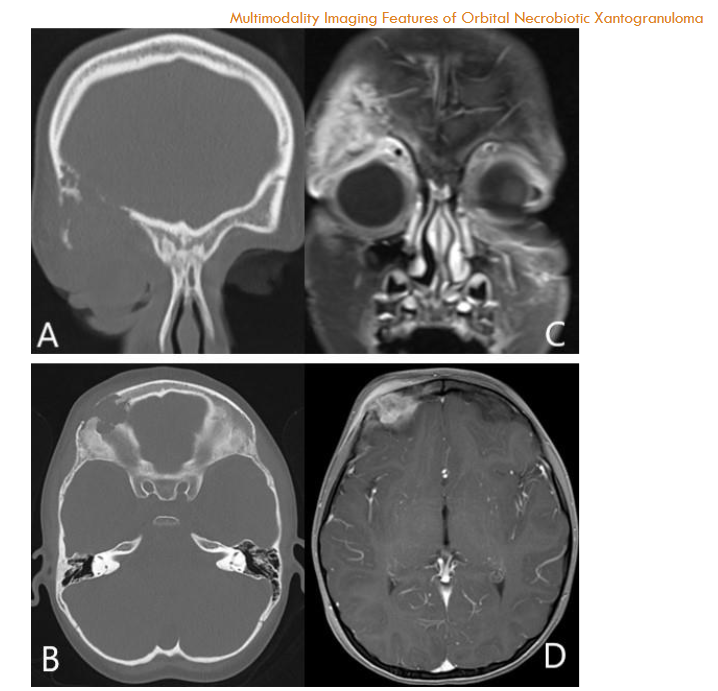

An orbital CT scan showed severe right orbital proptosis, right-sided pre- and post-septal soft tissue thickening with intraconal/retrobulbar space extension and diffuse thickening of the adjacent bone secondary to chronic inflammation without erosion. There was also diffuse paranasal sinus mucosal thickening.

Orbital MRI provided a clearer characterization of diffuse retro-orbital soft tissue thickening, involving the fat, extraocular muscles, and lacrimal glands, leading to pronounced right orbital proptosis and globe eversion. The right globe was flattened with optic nerve stretching. The retrobulbar mass extended posteriorly into the orbital apex without cavernous sinus involvement, and there was also further extension into the lateral face, affecting the temporalis muscle.

FDG PET/MRI was used to characterize the extent of the disease and determine the optimal site for tissue biopsy. FDG PET/MRI revealed multiple markedly FDG-avid cervical lymph nodes, focal intense uptake in the right parotid region, and focal uptake in the right orbital infiltrative mass with maximum Standardized Uptake Value (SUV) of 13. Guided by FDG PET/MRI, the patient underwent a biopsy of the most FDG-avid region of the right orbital mass, which was diagnosed as necrobiotic xanthogranuloma with increased IgG4 expression. The patient was treated with cyclophosphamide, corticosteroid, and high-dose IVIG followed by bone marrow stem cell transplantation and showed a good response in terms of both imaging and clinical evaluation. The genetic and histopathologic findings of this case are discussed in detail by Guess et al.